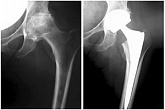

Еndoprosthesis of hip joint

In the late stages of arthrosis of the hip joint, medial fractures of the femoral neck in the older age group, the only way to recover is to replace the affected joint with an artificial joint - arthroplasty.

This method allows you to return the limb's limb, the full volume of movements in the affected joint, to save from constant pain and crunch during movements and, as a consequence, to return the patient to a full active life.

Below are presented X-ray photographs and photographs, illustrating the amount of motion in the affected joint before and after surgery.